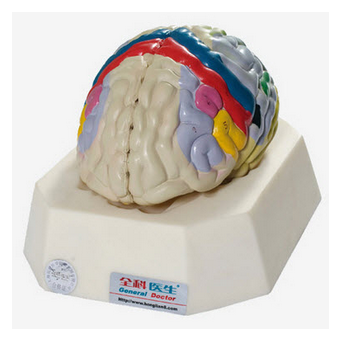

大腦皮質(zhì)分區(qū)模型 GD/A18206簡介:模型置于基板上,可分解成8部分,包括大腦半球,小腦和腦干等。著色顯示大腦皮質(zhì)分區(qū)。大腦皮質(zhì)分區(qū)模型,共顯示11個部位大腦皮質(zhì)分區(qū)常用為Brodmann分區(qū),將...